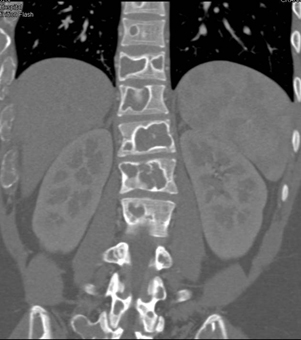

The best dx in this case is?

renal osteodystrophy

fibrous dysplasia

multiple myeloma

myelofibrosis